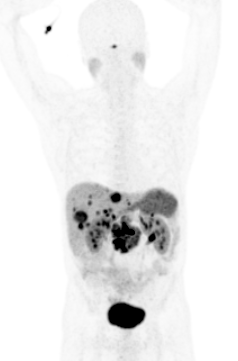

Le PET/CT au 68-Ga-DOTATOC est l'examen le plus sensible actuellement pour détecter des tumeurs neuroendocrines bien différenciées, car il détecte les récepteurs de la somatostatine (SSTR) fortement exprimés par les TNE. Cette méthode a remplacé la scintigraphie à l'Octréotide (Octréoscan), car elle offre une meilleure sensibilité et localisation de la lésion tumorale.

- Staging et re-staging de tumeurs neuroendocrines bien différenciées

- Contrôle de la thérapie

- Évaluation pour un traitement potentiel au Lutetium-177-DOTATATE